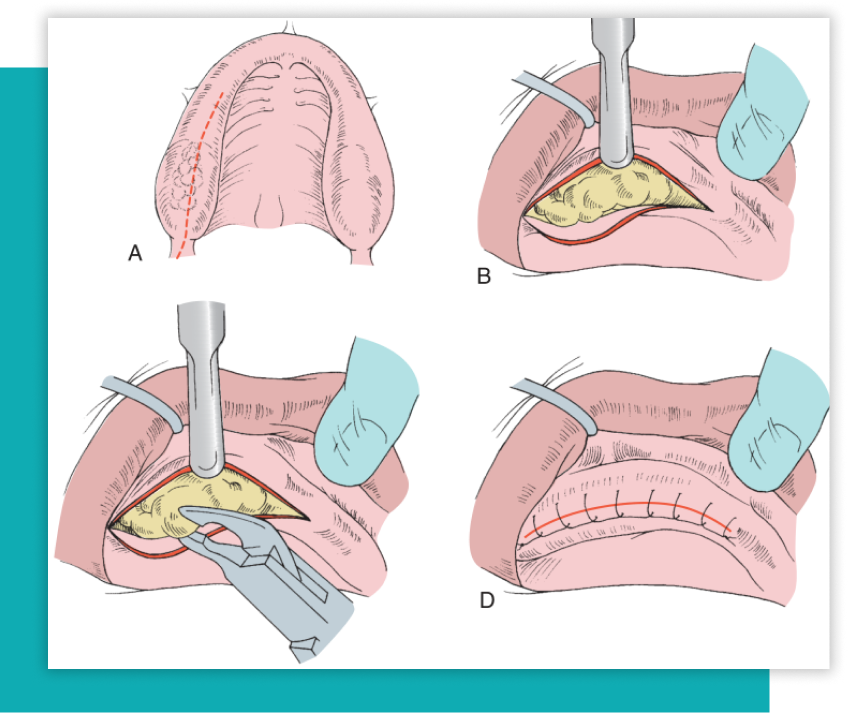

Cirugía Preprotésica

Es toda aquella cirugía que sea necesaria previa a utilizar una prótesis fija o removible, que puede incluir cirugía de exceso de encía (épulis), regularización del hueso de los maxilares, entre otros procedimientos que son necesarios para un buen ajuste y resultado de la prótesis final del paciente